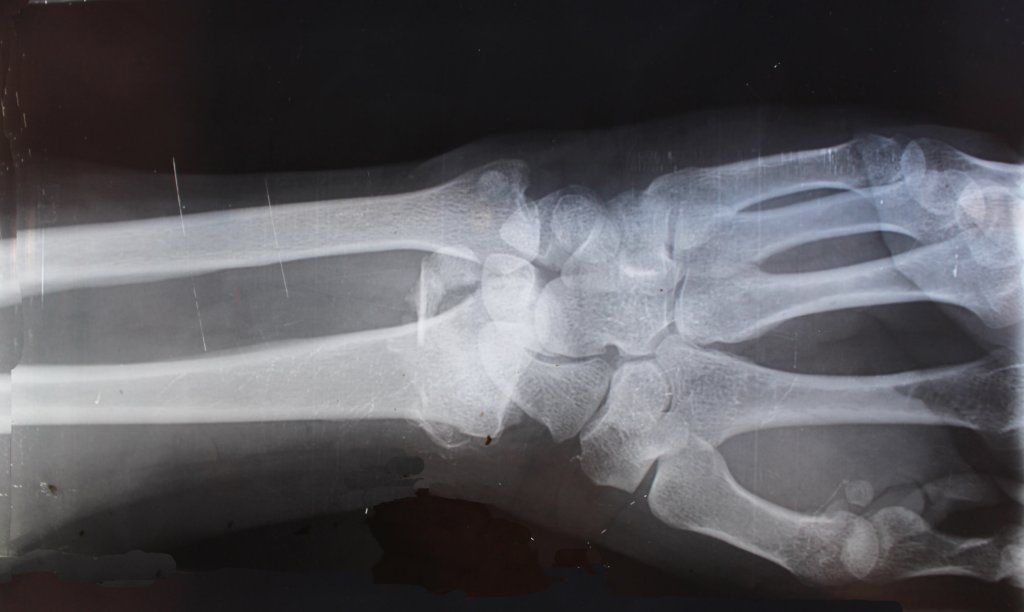

When an animal or human suffers a broken bone, sometimes a traditional cast is not a viable option due to the location or nature of the fracture. To address the problem, the University of Arizona professor Hamid Saadatmanesh has created a flexible carbon fibre fabric designed to be inserted inside and around a fractured bone. The fabric is filled with an inert polymer to inflate the fabric, which then acts as a permanent cast which cannot be rebroken.